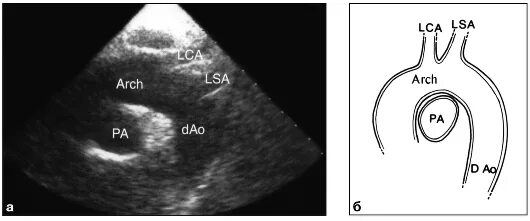

Уплотнение стенок аорты сердца на узи что